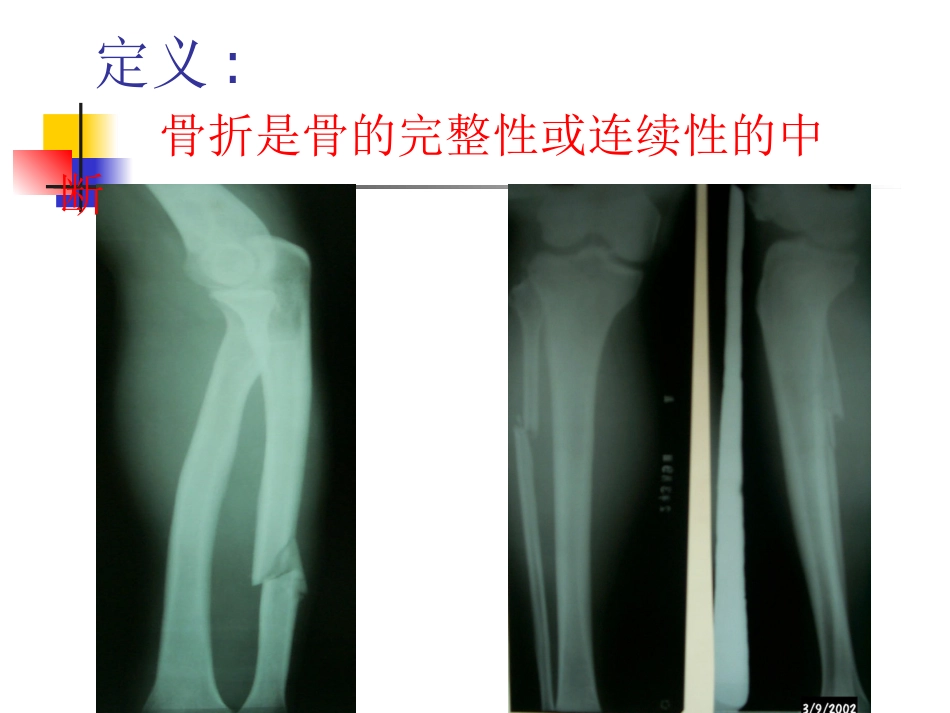

骨折的基本知识十二病区骨科护理组定义:骨折是骨的完整性或连续性的中断二、病因创伤创伤直接暴力-局部软组织损伤直接暴力-局部软组织损伤间接暴力-力的传导间接暴力-力的传导累积的劳损累积的劳损长时间长时间,,重复性重复性,,微弱的微弱的病理性骨折病理性骨折原发病+轻微外力原发病+轻微外力骨折的分类按骨折处皮肤、粘膜的完整性分①闭合性骨折②开放性骨折:按骨折的程度和形态分①不完全骨折:按其形态又可分为裂缝骨折、青枝骨折。②完全骨折:按骨折线的方向及其形态可分为横行骨折、斜形骨折、螺旋形骨折、粉碎性骨折、嵌插骨折、压缩性骨折、凹陷性骨折、骨骺分离,其中粉碎性骨折是指骨质碎裂成3块以上按骨折端稳定程度分①稳定性骨折②不稳定性骨折骨折段的移位由于各种因素,如外界暴力的性质、大小和作用方向,肌肉的牵拉,骨折远侧段肢体重量的牵拉,不恰当的搬运和治疗等影响,导致大多数骨折的骨折段均有不同程度的移位,常见有成角移位、侧方移位、缩短移位、分离移位、旋转移位,且几种移位可同时存在。骨折的临床表现局部表现:一般表现局部疼痛、肿胀和功能障碍。特有体征①畸形②异常活动③骨擦音或骨擦感。(骨折的异常活动和骨擦音或骨擦感不可反复多次检查)有些骨折如裂缝骨折和嵌插骨折,可不出现上述3个典型的骨折特有体征,应常规进行x线摄片检查,以便确诊。全身表现:休克发热X线检查:对骨折的诊断和治疗具有重要价值,一般应拍摄包括邻近1个关节在内的正、侧位片,骨折的并发症早期并发症:休克脂肪栓塞综合症重要内脏器官损伤重要周围组织损伤血管及神经损伤,脊髓损伤。骨筋膜室综合征晚期并发症:坠积性肺炎下肢深静脉血栓形成感染损伤性骨化又称骨化性肌炎关节僵硬这是骨折和关节损伤最常见的并发症急性骨萎缩缺血性骨坏死常见的股骨颈骨折后股骨头缺血性坏死缺血性肌挛缩这是骨折最严重的并发症之一,典型的畸形是爪形手和爪形足。骨折的急救现场急救不仅要注意骨折的处理,更重要的要注意全身情况的处理。1.抢救休克2.包扎伤口3.妥善固定固定是骨折急救的重要措施,4.迅速转运骨筋膜室综合征骨筋膜室综合症(psteofascialcompartmentsyndrome)即由骨,骨间膜,肌间隔和深筋膜形成的骨筋膜室内肌肉和神经因室内压力增高,急性缺血而产生的一系列早期症候群,最多见于前臂掌侧和小腿。主要表现病情观察:5ppain剧烈疼痛转无痛Pallor潮红转苍白或发绀Paralysis肌肉麻痹Paresthesia感觉异常Pulselessness无脉一旦确诊,立即松解所有外固定物,将肢体放平,不可抬高,并尽量减少患肢活动一旦确诊,立即松解所有外固定物,将肢体放平,不可抬高,并尽量减少患肢活动。处理:应紧急切开深筋膜及肌间隔以缓解间室压力骨折的治疗原则1.复位标准①解剖复位②功能复位方法①手法复位②切开复位固定2.固定方法有外固定和内固定3.功能锻炼1-2周患肢肌肉的主动收缩活动2周后开始骨折上下关节活动晚期全面练习骨折愈合过程1.血肿机化期约在骨折后2周完成。2.原始骨痂形成期包括膜内化骨、软骨内骨、内骨痂和外骨痂、环状骨痂和髓腔内骨痂形成等一系列过程,达到临床愈合,一般需4~8周。3.骨痂改造塑形期约需8~12周骨折临床愈合标准1.局部无压痛及纵向叩击痛。2.局部无异常活动。3.X线片显示骨折处有连续性骨痂,骨折线已模糊。4.拆除外固定后,上肢能向前平举1㎏重物持续1分钟;下肢部扶拐杖能在平地连续步行3分钟,并不少于30步;连续观察2周骨折处不变形。临床愈合时间为最后一次复位之日至观察达到临床愈合之日所需的时间。达到临床愈合后,病人可拆除固定,但检查肢体异常活动和肢体负重情况时宜慎重,不宜于解除固定后立即进行影响骨折愈合的因素1.全身因素:年龄健康状况。2.局部因素:骨折的类型和数量。骨折部位的血液供应软组织损伤程度软组织嵌入感染。3.治疗方法骨折延迟愈合,不愈合和畸形愈合1.骨折延迟愈合即骨折经过治疗,超过一般愈合时间,骨折断端仍未出现骨折连接。2.骨折不愈合即骨折经过治疗,超过一般愈合时间,且经再度延长治疗时...